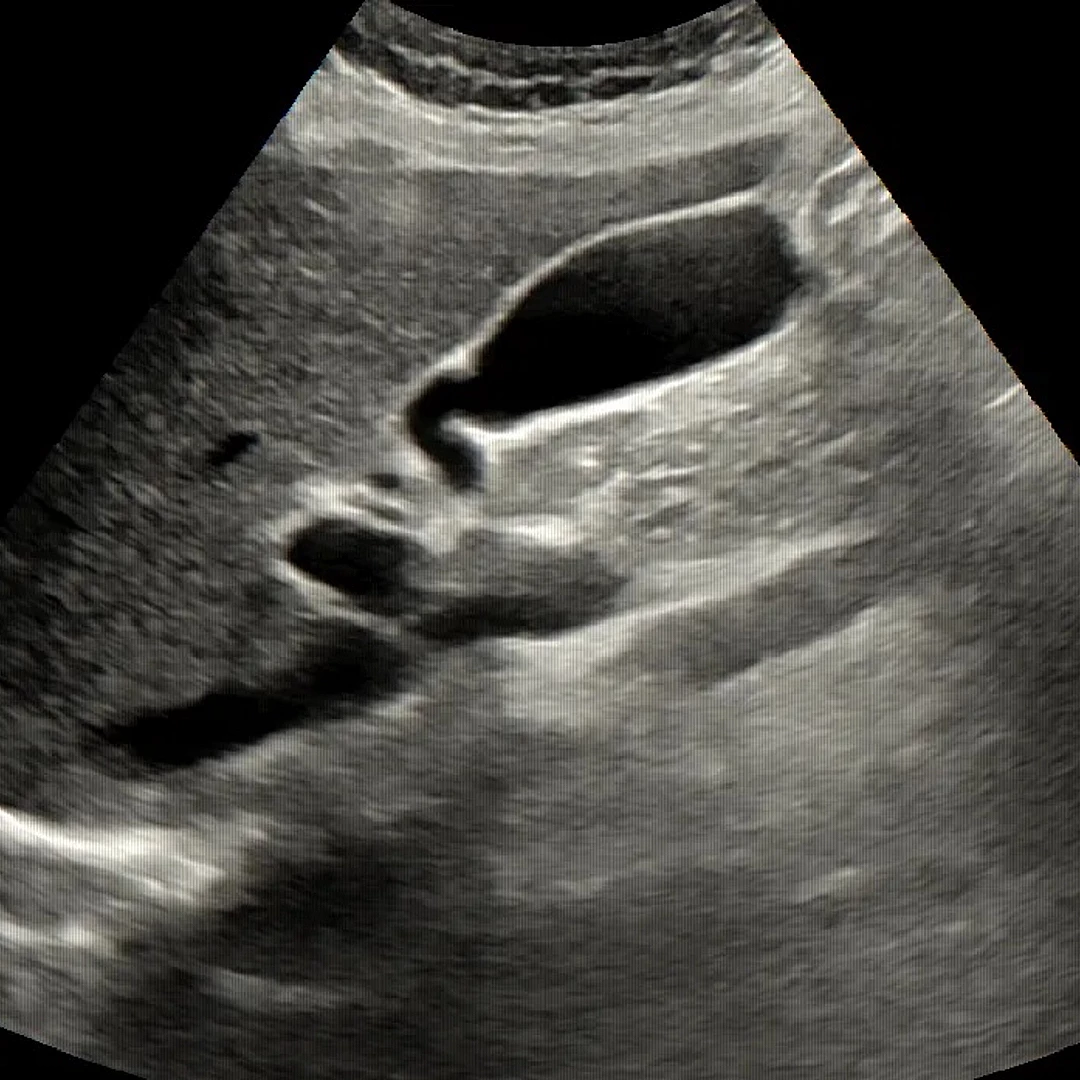

Abdominal Ultrasound

Abdominal Ultrasound uses sound waves to visualize organs like the liver, kidneys, gallbladder, and pancreas. It’s a non-invasive, radiation-free scan ideal for diagnosing pain, swelling, or abnormalities in the abdomen.